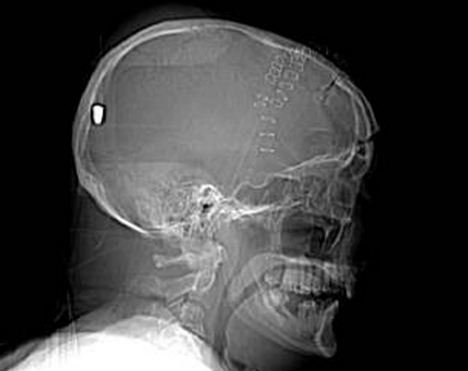

據(jù)英國(guó)《每日郵報(bào)》5月11日?qǐng)?bào)道,英國(guó)一名61歲的老人上個(gè)月19日在花園干活時(shí)被一顆流彈擊中腦部竟奇跡存活,目前他半身癱瘓但無(wú)生命危險(xiǎn)。5月10日,警方為了破案公布了彼得先生的腦部掃描圖片,希望知情者提供相關(guān)線索。

事情的經(jīng)過是這樣的,彼得在整理花園的時(shí)候突然摔倒在地不省人事,他的家人還以為他中風(fēng)了,但醫(yī)院對(duì)其大腦掃描后卻發(fā)現(xiàn)了令人驚悚的事實(shí):一顆子彈不知由于何種原因從左眼窩進(jìn)入他的大腦,并深深植入其腦后部。但不可思議的是彼得竟然活了下來,雖然身體部分癱瘓且失去了語(yǔ)言和記憶能力。

醫(yī)生說開顱取彈手術(shù)風(fēng)險(xiǎn)巨大,很可能危及彼得生命,所以只能放棄這個(gè)計(jì)劃。彼得先生已經(jīng)被告知事故經(jīng)過,但他自己什么也想不起來了,醫(yī)生認(rèn)為他患了健忘癥。除了損傷左眼視力外,彼得先生身體右下半部分也已癱瘓。他的發(fā)音都很含糊,記憶也是支離破碎的,目前大部分時(shí)間都在睡覺,但病情還算穩(wěn)定。

負(fù)責(zé)調(diào)查此案的警官史蒂夫表示:“這可能是我調(diào)查過的最詭異的一個(gè)案子了。”經(jīng)過對(duì)掃描圖片的鑒定,警方彈道專家賈爾斯認(rèn)為這顆子彈很像是從一種通常用于射殺兔子的.22口徑獵槍里射出的。

“如果在10碼外開這種槍,子彈會(huì)穿透彼得的腦部,但若是從800到1000碼以外,子彈會(huì)失去大部分的沖擊力,只能穿透軟組織。所以說,在這個(gè)距離內(nèi),子彈若射中彼得腦殼會(huì)被彈回,不可能進(jìn)入腦中,”賈爾斯說。